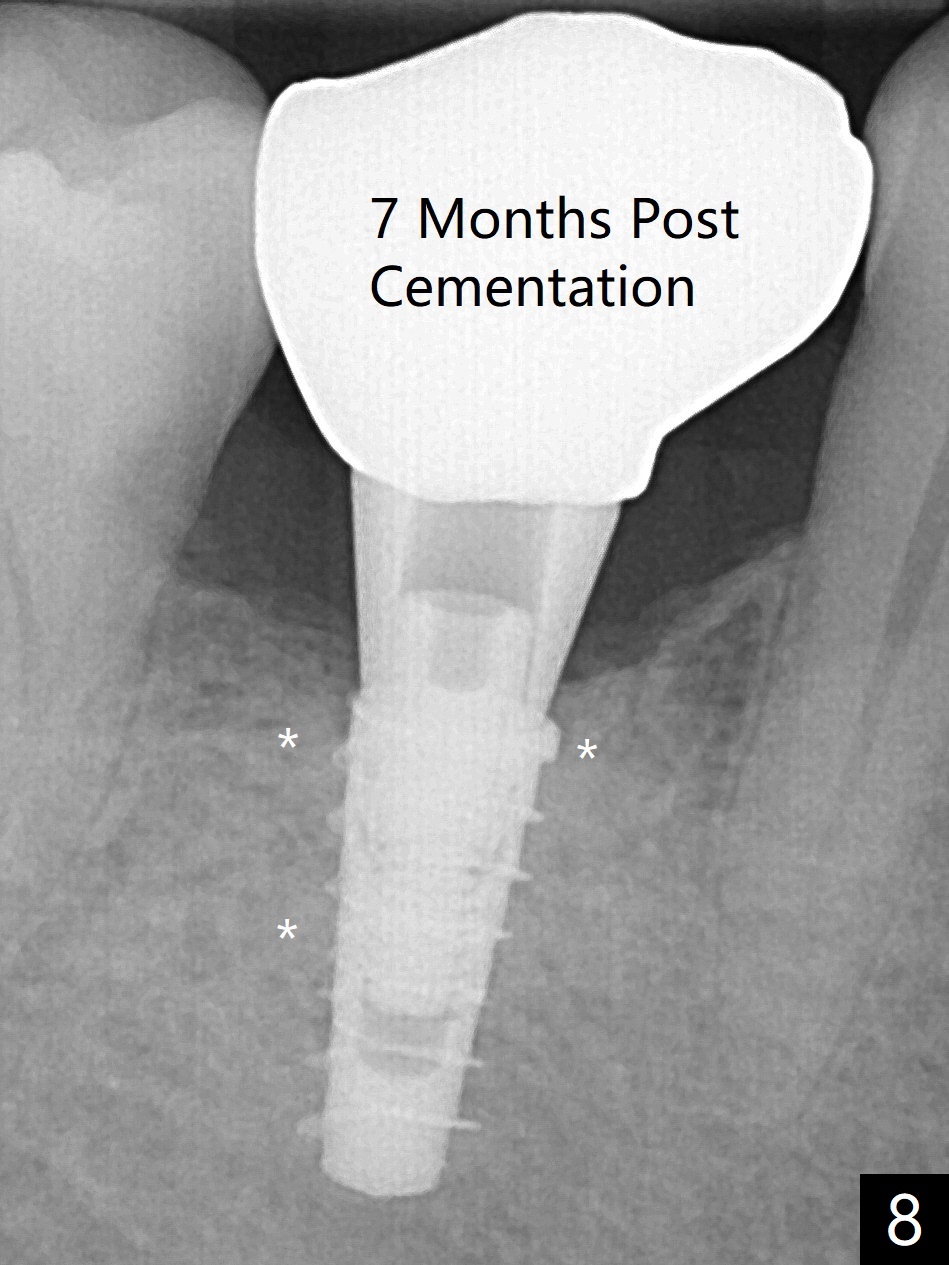

The retained deciduous tooth (lower right 2nd molar, Fig.1 T) has buccal apical infection and recession. After extraction, the initial depth of osteotomy is 11 mm over the flat socket bottom (Fig.2) without visible Mental Loop. Following 3.8 mm Magic Drill for 11 mm, a 4x11 mm dummy implant is placed partially due to hard bone; it appears that the apical osteotomy (Fig.3 yellow outline) overlaps the Mental Loop (red dashed line). For safety, a 4x9 mm IBS implant is placed with insertion torque 40 Ncm; a 5x5.7(4) mm abutment is immediately placed for an immediate provisional to cover the large socket and keep Vera graft in place (Fig.4 *). There is no postop paresthesia, probably due to the fact that the osteotomy is lingual to the Mental Loop. The provisional remains in place 7 days postop; its margin (Fig.5 arrow) covers the socket. The margin of the provisional is trimmed 1 month postop. Impression is taken nearly 3 months postop (Fig.6). The buccal plate looks atrophic 3 months postop (Fig.7 (immediately before cementation)), although there is no sign of periimplantitis. In the future, insert the immediate provisional inside of the buccal gingiva to make the buccal gingiva look bulky instead of buccal to it (Fig.5). The second drawback of placing an implant at the deciduous tooth area is that the crown is wide mesiodistally if orthodontic treatment is not rendered. Although there is lower anterior crowding, the patient declines orthodontic treatment. The bone density around the implant increases 7 months post cementation (Fig.8 *). The higher density bone seems to extend coronally 1 year 7 months post cementation (Fig.9). The dense bone apparently extends toward the abutment as well 3 years 5 months post cementation (Fig.10 curved arrows).